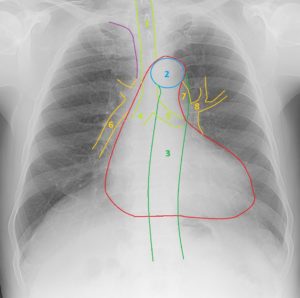

Анатомия коронарных артерий: КТ-изображения

Раздел: Снимки успеха